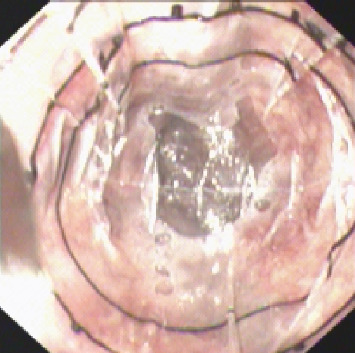

Background: Esophageal variceal (EV) diameter is a critical, independent risk factor for hemorrhage, and plays a key role in guiding choices of endoscopic treatment techniques. We developed a novel tool, the virtual ruler (VR), which offers increased precision and expediency in EV diameter (EVD) measurements. This study investigates the clinical value of VR for assessing EVD during the endoscopic treatment of cirrhotic EVs. Methods: We performed a retrospective multicenter review of 345 cirrhotic patients with EVs who received endoscopic treatment. EVD was measured using VR, and several outcomes, including rebleeding rates, vascular eradication rates, mortality, and complication incidences, were compared in patients stratified by EVD as measured by both VR and endoscopists. Results: There was moderate agreement between VR and endoscopist measurements of EVD (Kappa = 0.591, p < 0.001). In patients with EVD > 1 cm, the VR group had a lower rebleeding rate after endoscopic treatment compared to the endoscopist group (3.8% vs. 11.3%; p=0.048). No significant between-group differences in outcomes were noted in patients with EVD ≤ 1 cm. Additionally, comparisons of endoscopic variceal ligation and endoscopic injection sclerotherapy within the VR-based diameter groups showed no substantial differences in treatment efficacy or adverse events (p > 0.05). Conclusion: Using VR to accurately measure EVD may help decrease endoscopist misjudgment of larger EVD values and may reduce postoperative rebleeding rates after endoscopic treatment. VR holds potential clinical significance in guiding endoscopic EV treatment. Trial Registration: Clinical Trial Registry identifier: ChiCTR2200064028.

Abstract Image